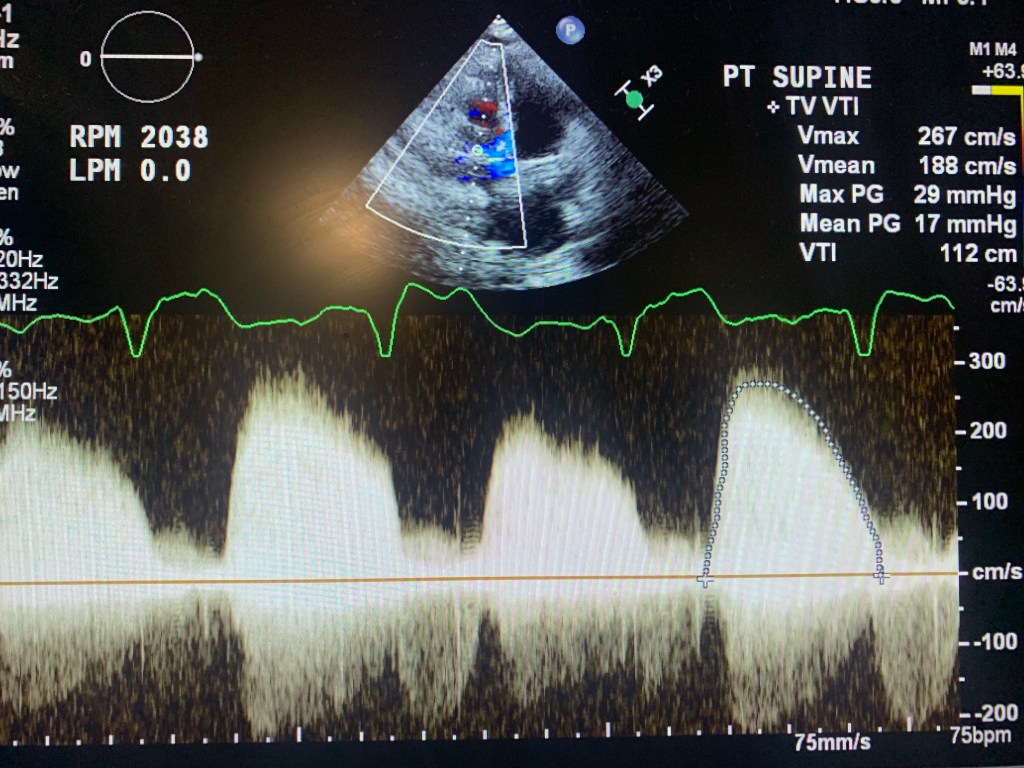

🔘 during RAMP studies: theres no LV dimention change with increased pump support/RPM

Below are a few images and videos of RVAD and changes in RAMP study I did recently